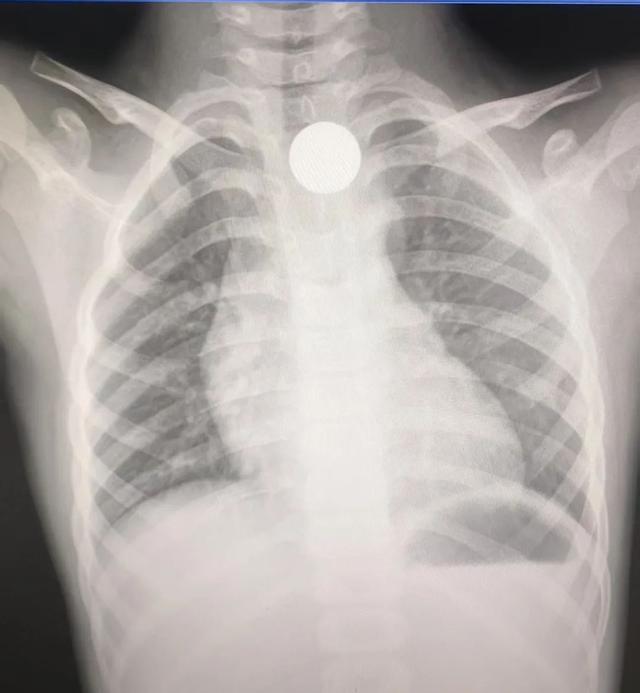

1月27日晚11点多,6岁的小帅(化名)在玩耍时一个不留神将一枚硬币吞进了肚子里,小帅的父母心急如焚,立刻带着孩子赶到宁乡市中医医院。经过CT检查,发现那枚硬币正卡在食管上段。

因为孩子晚上九点多还有吃东西,考虑到胃里还有不少没来得及消化的食物,若是直接进行麻醉胃镜下取异物可能会发生误吸的危险,消化内镜医疗团队经过谨慎考虑,决定为孩子试行普通胃镜取异物。

检查发现食管上段有大量液状食物,再加上孩子因为害怕极度不配合,医疗团队反复和家长确认,得知吞入的异物是硬币,而不是纽扣电池等高危物品后,为了确保手术安全,决定先严密观察,等食物消化一些后再取出异物。

最终,顺利取出了硬币,整个手术过程非常顺利。